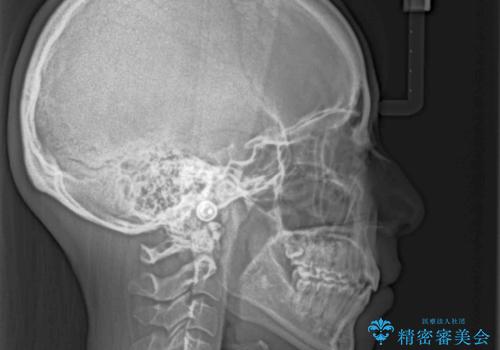

2年から2年半の治療期間を想定しており、予定通りの期間で無事に終了することができました。

唇や顎先に力を入れないなくてもスムーズに唇を閉じることができるようになりました。